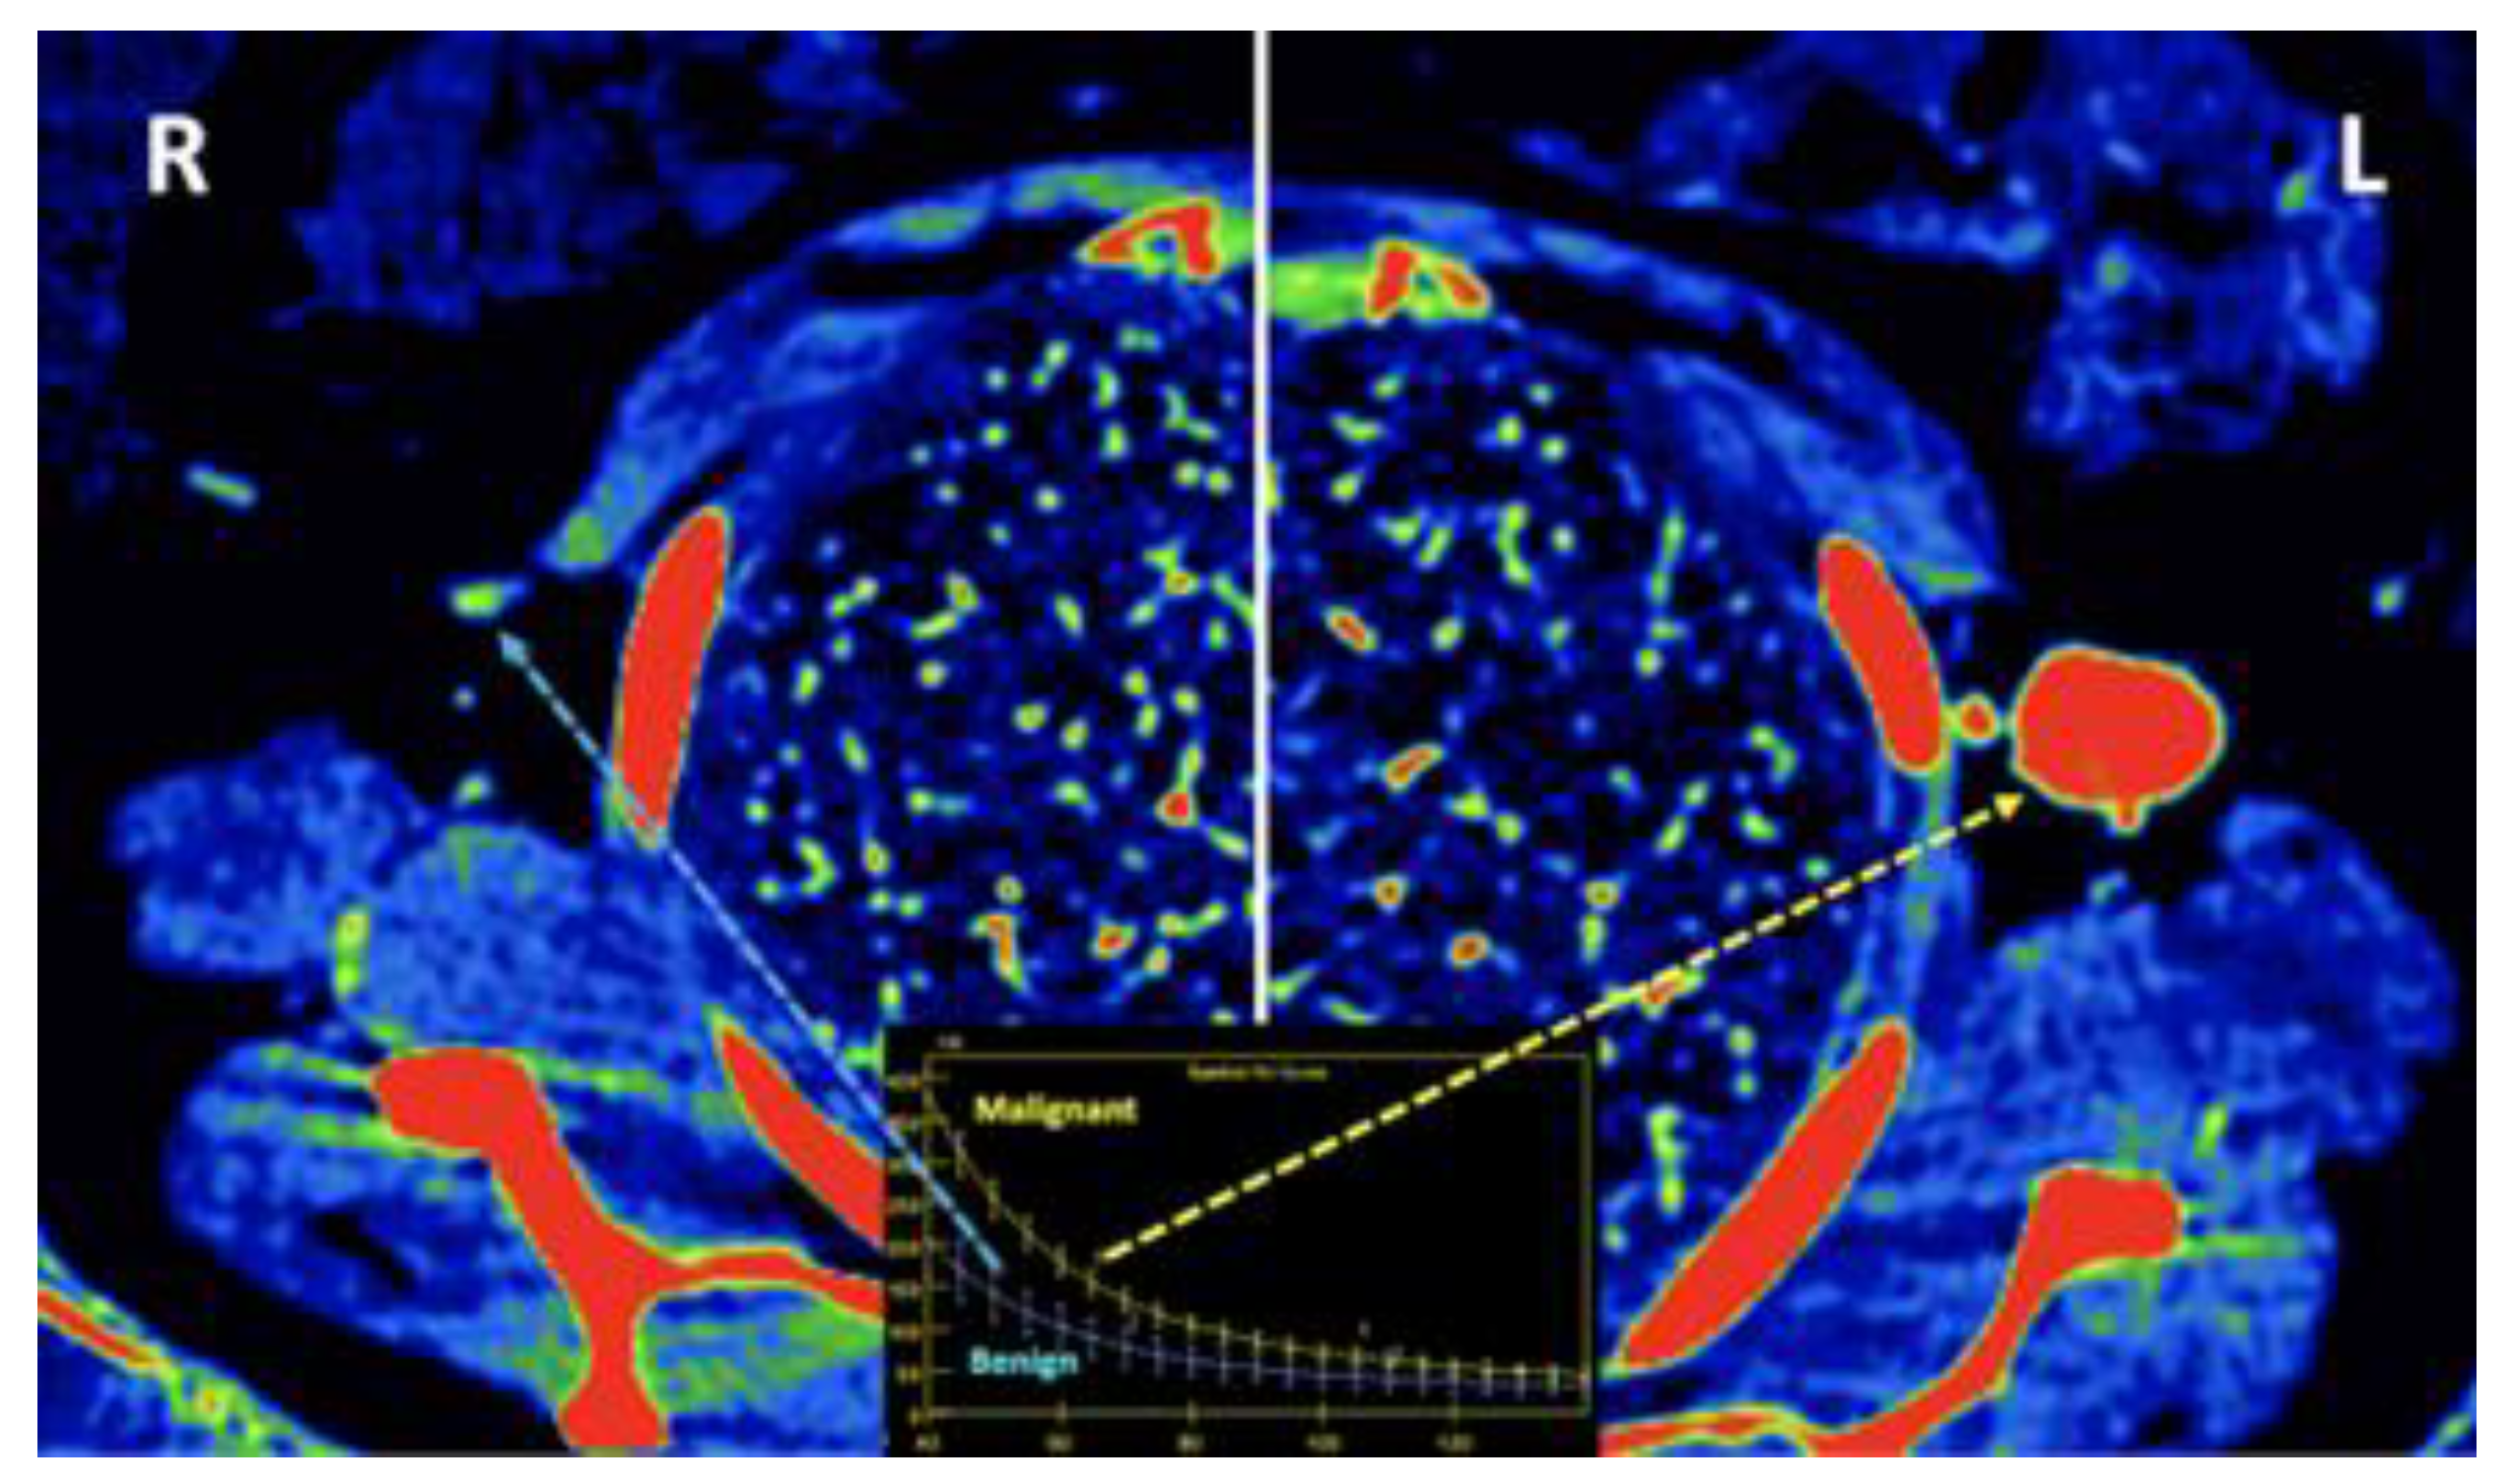

- Currently, there is not a widely reported use of DECT in clinical management of prostate cancer. However, DECT imaging may facilitate the depiction of focal areas of increased enhancement in the periphery of the prostate at contrast-enhanced CT that may represent a clinically significant cancer and deserve further workup [42] [Figure 13].